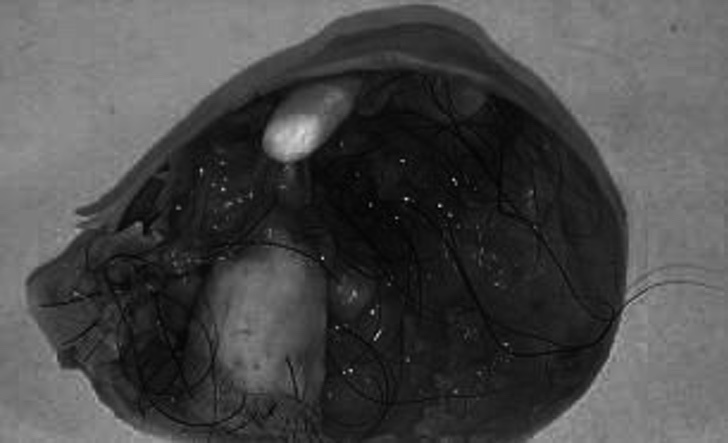

Hasta que finalmente pudo saber lo que padecía, según relató la revista Woman´s Healt, lo que encontraron los doctores y que le causaba esos dolores terribles, se trataba de un quiste dermoide ubicado en el ovario derecho.

Según informó este medio, la malformación encontrada en el ovario estaba conformada con tejido, pelos y dientes. La misma Calle Hack describe al quiste como “un pequeño monstruo”.

Fue cuando la doctora Meghan Sheldon expuso que aunque este quiste era benigno, pues no se conformaba de células cancerígenas, pudiera haber sido peligroso por su tamaño.

En ese momento, la doctora recomendó que lo mejor sería extirpar el quiste de inmediato, pues esto seguiría provocando problemas y a la larga podría desarrollar cáncer.